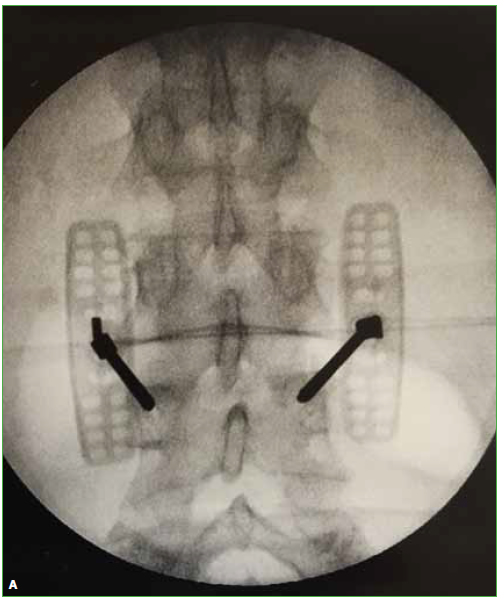

Ante la falta de mejoría con las medidas conservadoras, se decide realizar cifoplastia transpedicular biportal L4 con toma de biopsia (Figura 6), lo que se lleva a cabo sin complicaciones. Los análisis preoperatorios de rutina no revelaron alteraciones.

Figura 6. A y B.

Radioscopia intraoperatoria del procedimiento de cifoplastia, columna lumbar de frente y de perfil. Se observa cemento en la vértebra L4.